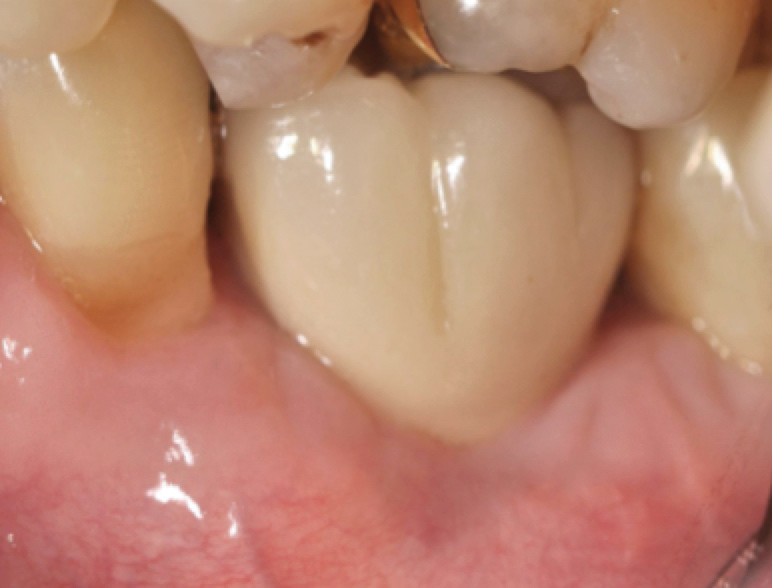

Fig 45. The definitive crown tooth No. 26 seated in place and provisionally cemented. The recession defect was eliminated with the removal and replacement of a new implant in the proper position.

Figure 45

The crown and screw-retained custom abutment were removed, and a surgical cover screw was placed into the implant, thereby allowing spontaneous gingival augmentation in situ (Figure 33 and Figure 34). Note that the lingual aspect of the implant site was significantly more coronal than the labial aspect, which was positive because the defect would be limited to a facial–lingual defect. A fixed RBR bridge was cemented on the adjacent teeth and used as a tooth-supported transitional provisional restoration (Figure 35). A few weeks were allotted to let the soft tissue heal and migrate around the cover screw (Figure 36) to see if there would be complete coverage, thereby allowing a soft-tissue augmentation procedure to be performed with primary flap closure as in clinical scenario No. 2. The major obstacle in achieving a positive tissue response was that the implant depth was also deficient because the implant–abutment connection was at the level of the free gingival margin. It was decided that the best treatment option would be to remove the implant. A high-powered reverse-torque device (Fixture Remover Kit, NeoBiotech, www.neobiotechus.com) was used to remove the implant atraumatically (Figure 38 through Figure 41). The implant socket was allowed to heal for several months not unlike an extracted tooth (Figure 42). A new implant was placed in a better position from both a restorative and esthetic perspective (Figure 43), and after a few months of healing, a new crown was made (Figure 44). A satisfactory functional and esthetic result was achieved (Figure 45 and Figure 46) without employing pink porcelain.